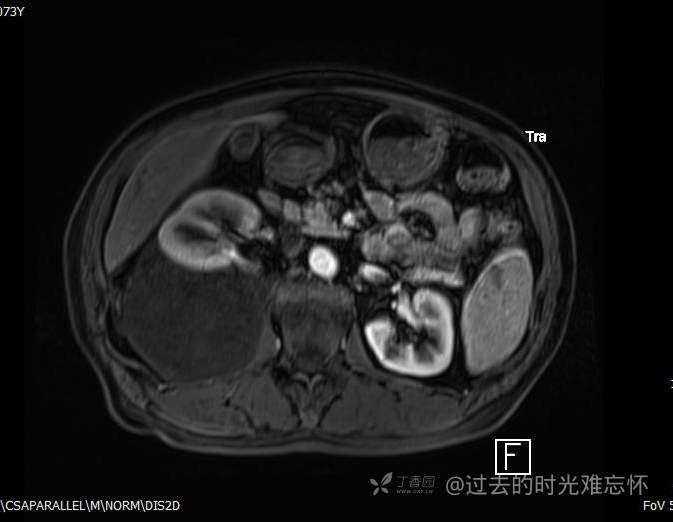

患者性别:男

患者年龄:73岁

主诉:咳嗽1月余。曾有血尿一次。后背部酸痛不适1-2年左右,无明显消瘦。

辅助检查:CT MRI

临床诊断:占位

治疗经过:手术

增强

黏液样脂肪肉瘤 (12)